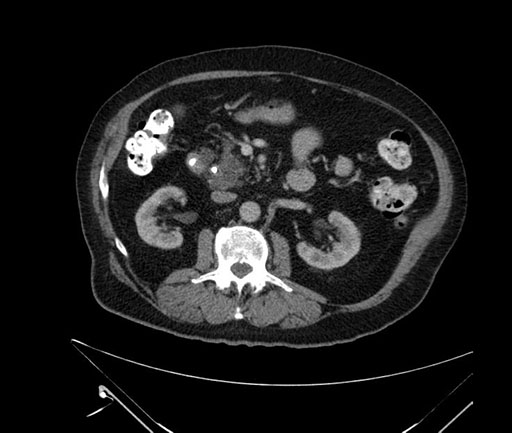

Whipple (pancreaticoduodenectomy) [case 7]

Axial - stented

Imaging analysis

Based on your CT findings, which issue(s) would give reason for "planned slowing down moment(s)" in this case?

Considering a standard Whipple procedure, what step(s) of the operation would you do differently in this case?